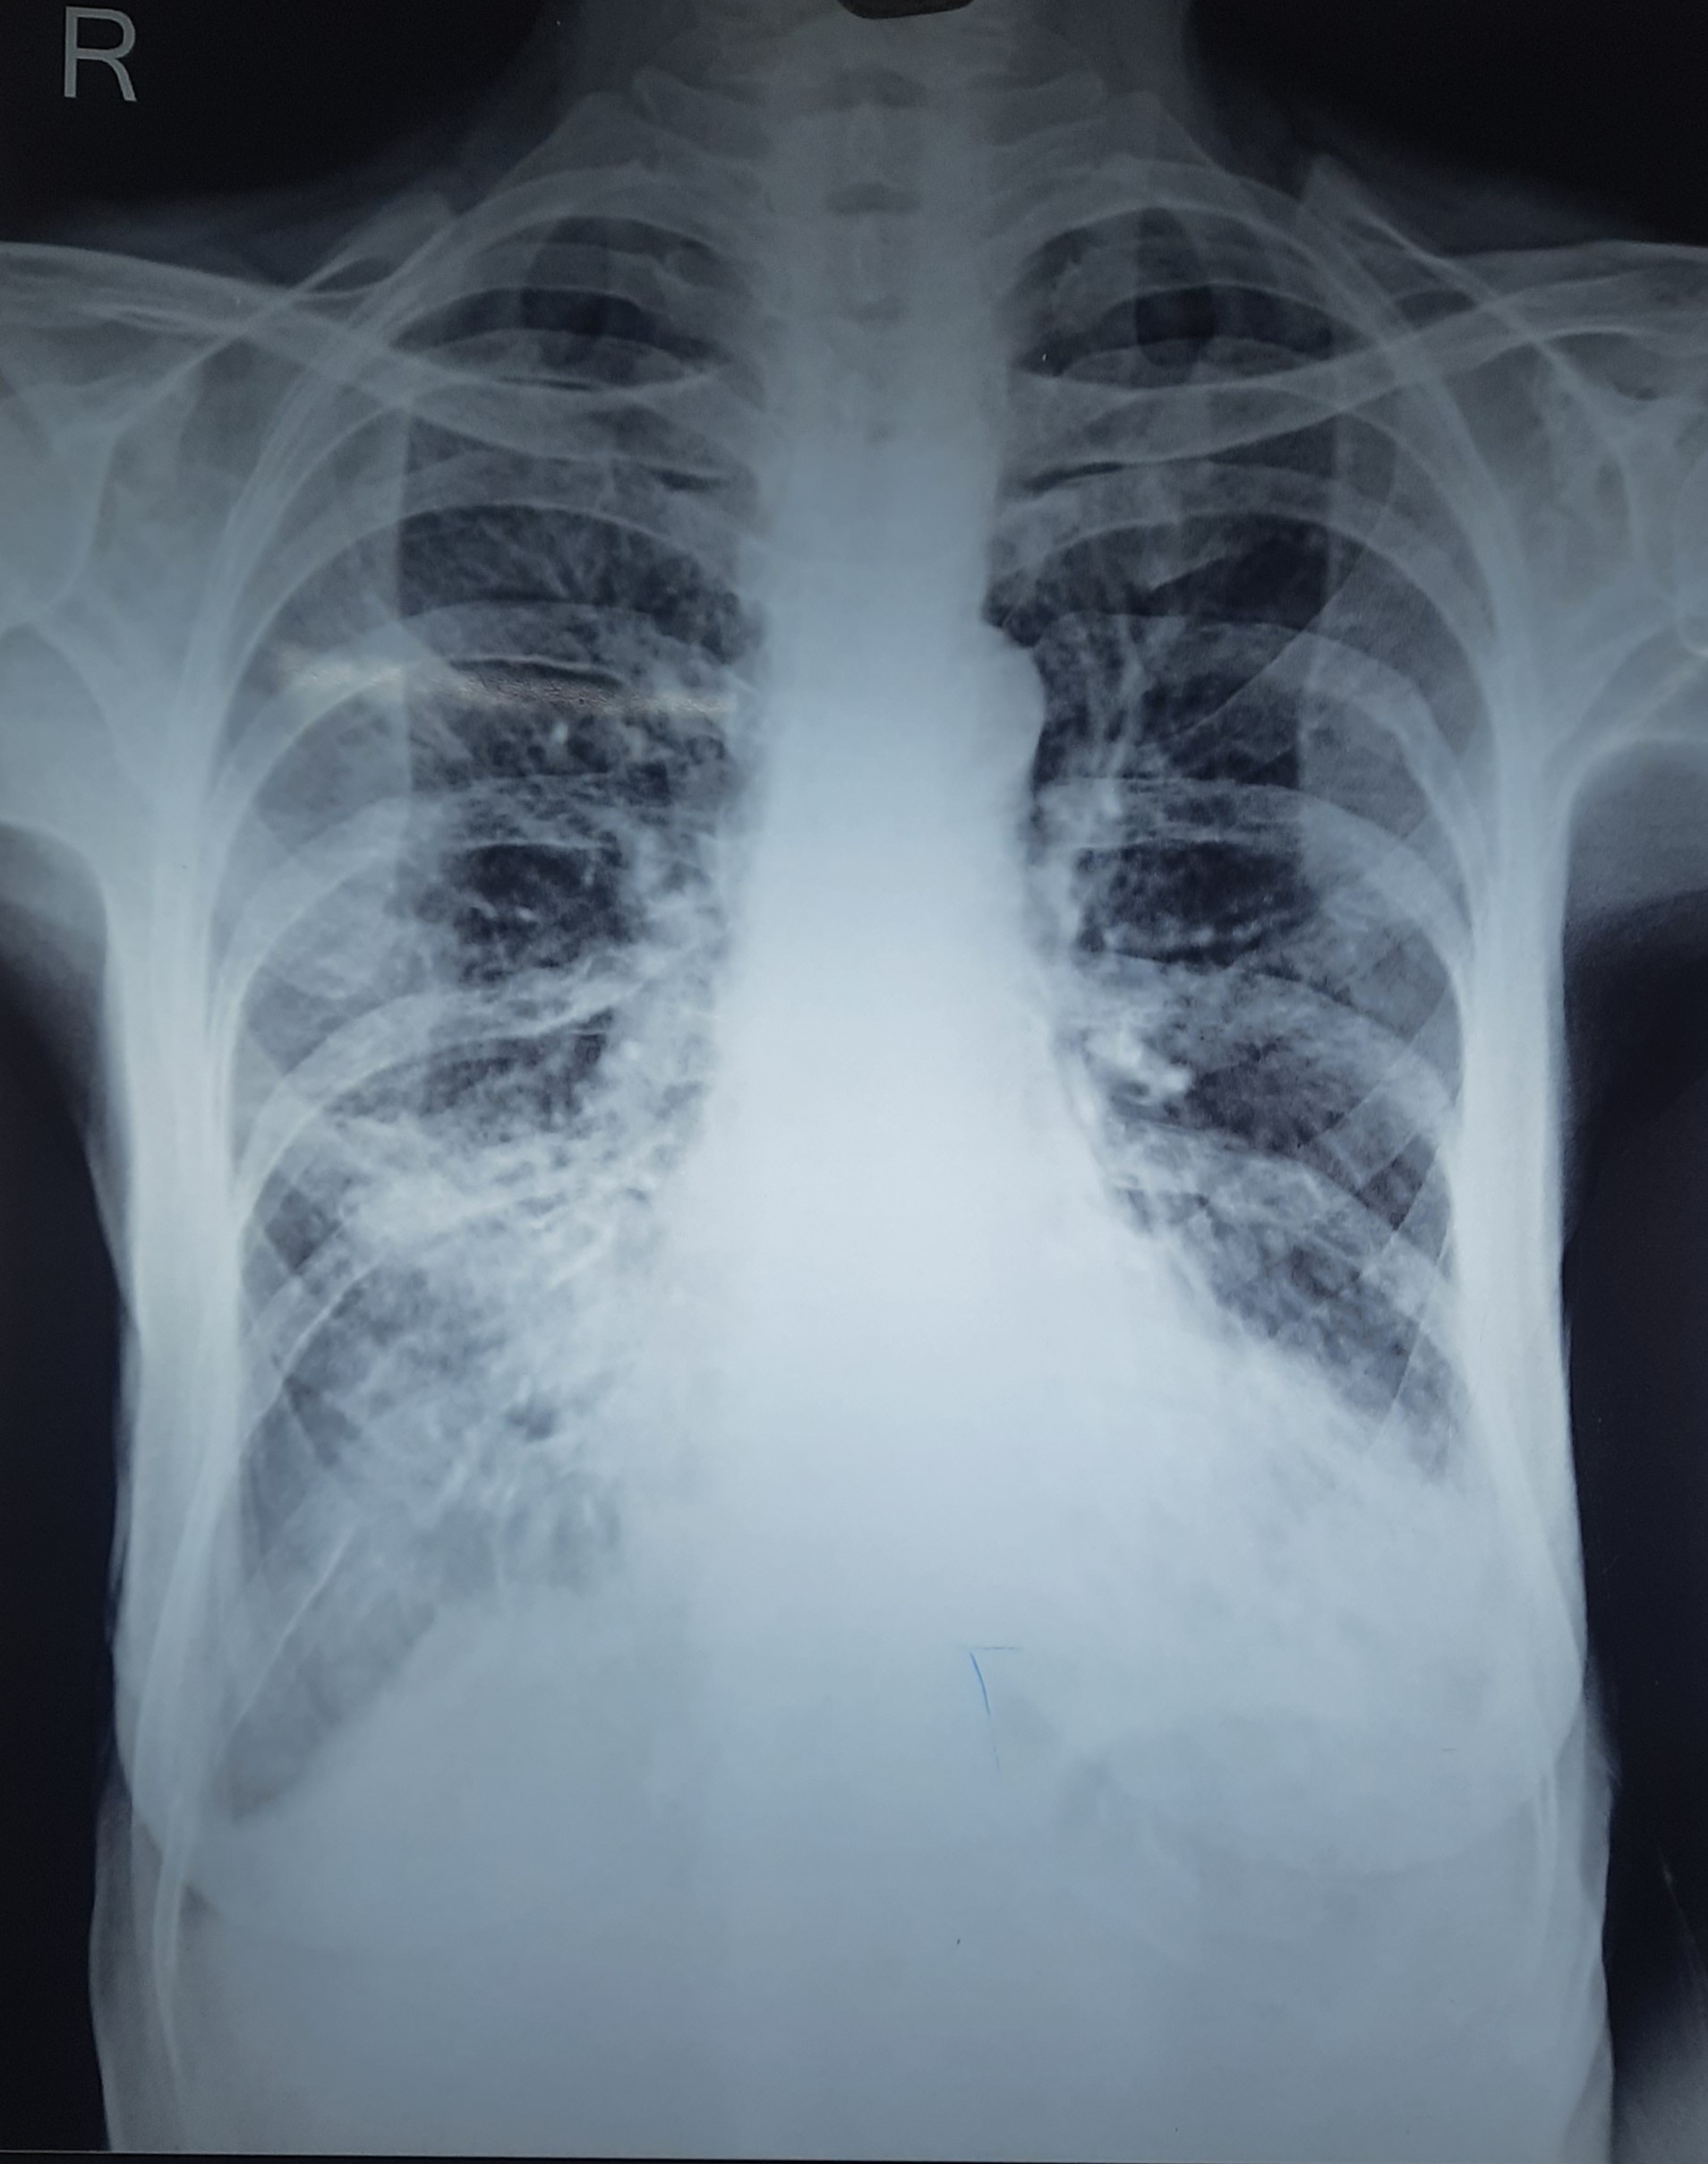

Result awaited (Suspected TB/Non-TB) | Left Upper Zone Cavity Present With Bilateral Upper Zone & Mid zone Infiltration | Abnormality visible on x-ray |

View |